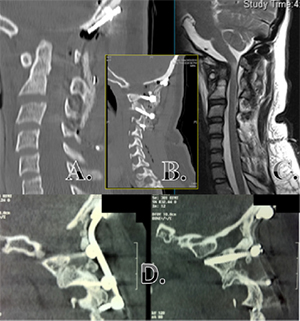

The patient underwent a 7-hour occiput–C3 internal fixation

and fusion. Through a suboccipital approach, internal fixation was

achieved with C1 lateral mass, C2 pars and C3 lateral mass screws,

including an occipital plate and rod with iliac crest bone graft bilaterally.

Subtraction osteotomy of the C2 pars was performed to reduce

the lateral mass of C1 onto the superior facet of C2 (Fig. 2).

An iliac crest bone graft with tricalcium phosphate was used.

Immobilization in a Miami-J orthosis for 3 months was used postoperatively.

CT scans showed solid fusion at 6 months (Fig. 3).

Fig. 3. Post-operative images of a patient with Down syndrome: (A) mid-sagittal CT

scans demonstrating occipital plate and reduction of occipital–C1 subluxation; (B)

para-sagittal CT scans demonstrating lateral mass screw placement in C1–3; (C) T2-

weighted MRI demonstrating improvement in the degree of canal stenosis at the

occipital–cervical junction; and (D) para-sagittal CT scan at 6 months demonstrating

solid fusion.